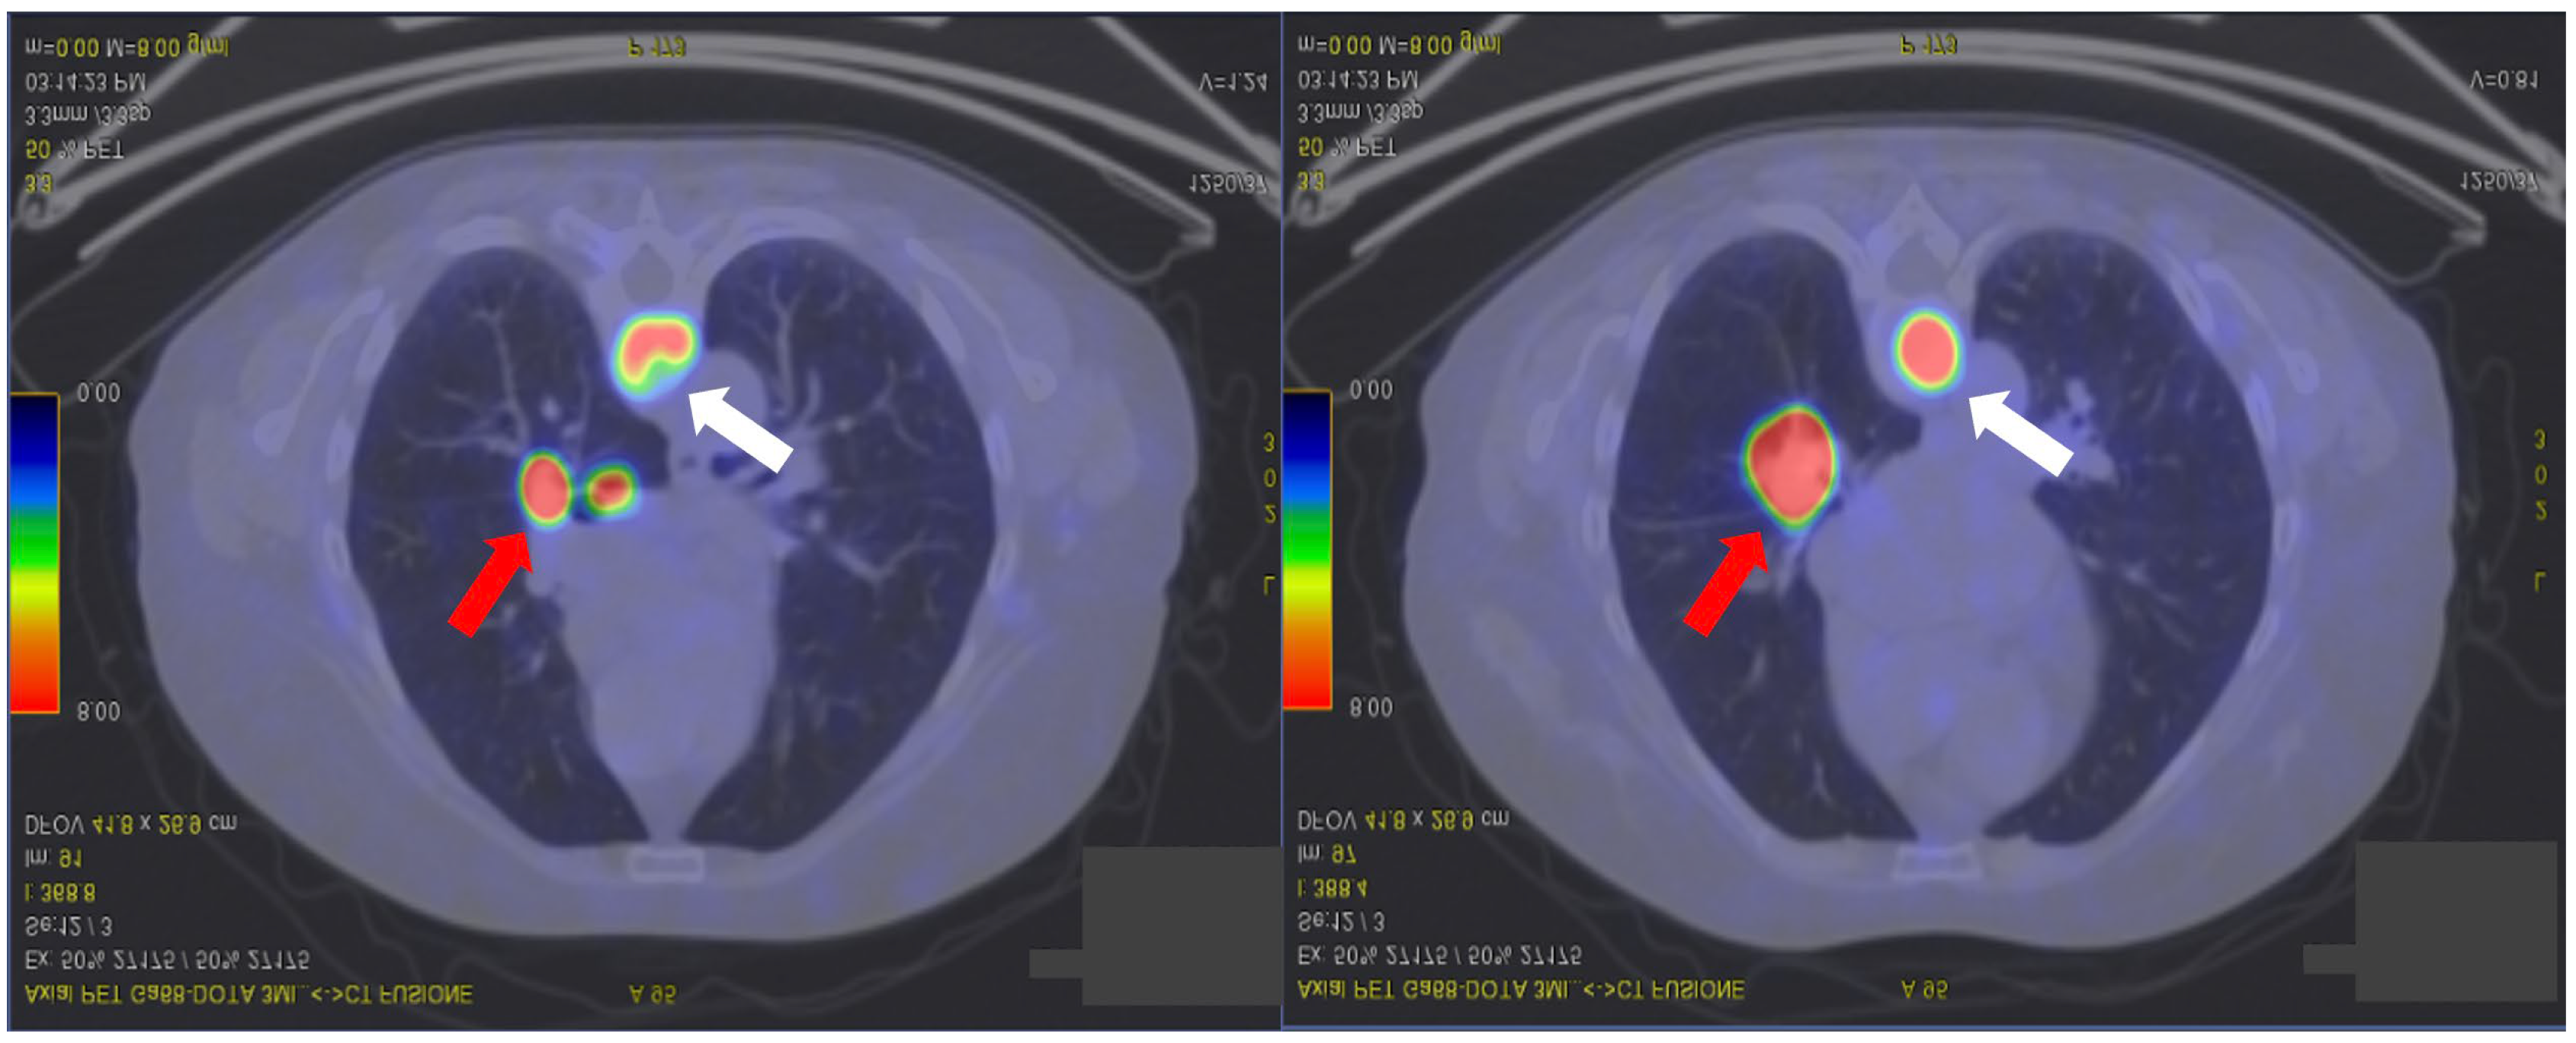

2. Case Presentation